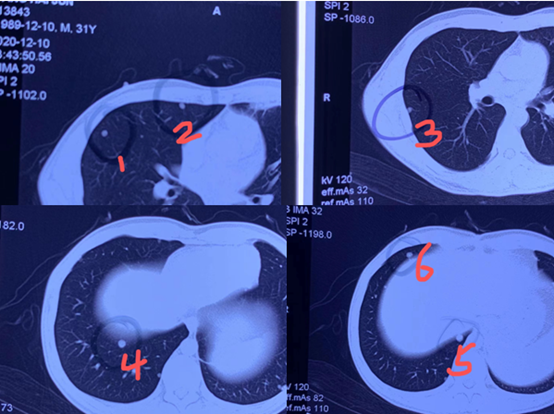

Perbandingan tiga nodul paru sebelum dan sesudah cryoablasi

Ini adalah kasus pasien kanker hati dengan metastasis paru-paru, di mana ditemukan enam nodul paru-paru. Mengingat pasien tersebut relatif muda dan dalam kondisi kesehatan yang baik, terutama dengan fungsi paru-paru yang baik, krioablasi digunakan untuk mengobati keenam nodul dalam satu sesi, menghindari trauma lebih lanjut dan mengurangi beban keuangan.